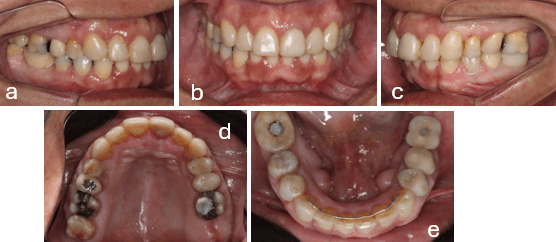

En el análisis facial frontal presenta simetría facial, buen sellado labial, tercios faciales equilibrados, mesofacial. (fig.1a). Línea media dentaria superior desviada a la derecha con respecto a la línea media facial. (fig.1b) En el lateral reveló un Patrón I, perfil recto. (fig.1c)

En el examen intraoral se observa Mal Oclusión de Clase II, división 2 subdivisión izquierda Tipo 2. Relación Molar ½ Clase II izquierda, Clase I derecha. Relación canina Clase I derecha, ½ Clase II izquierda. La línea media superior e inferior coincidentes. Overbite de 2 mm Overjet de 2 mm y mordida cruzada del 1.2 (fig. 2 a, b y c)

Arco superior con atresia y apiñamiento leve, molares 1.6 y 2.6 extruidos; 2.1 con cambio de coloración por tratamiento de endodoncia previo (Figura 2d), arco inferior forma triangular y apiñamiento moderado; corona del 4.6 defectuosa. Restauración oclusal de amalgama de 4.8 fracturada; dentición permanente con ausencia de piezas dentarias 3.6, 3.7 y 4.7 (fig. 2e).

Figura 2.- Fotos Intraorales Iniciales.

a) Lateral derecha b) Frontal c) Lateral izquierda d) Oclusal superior e) Oclusal inferior